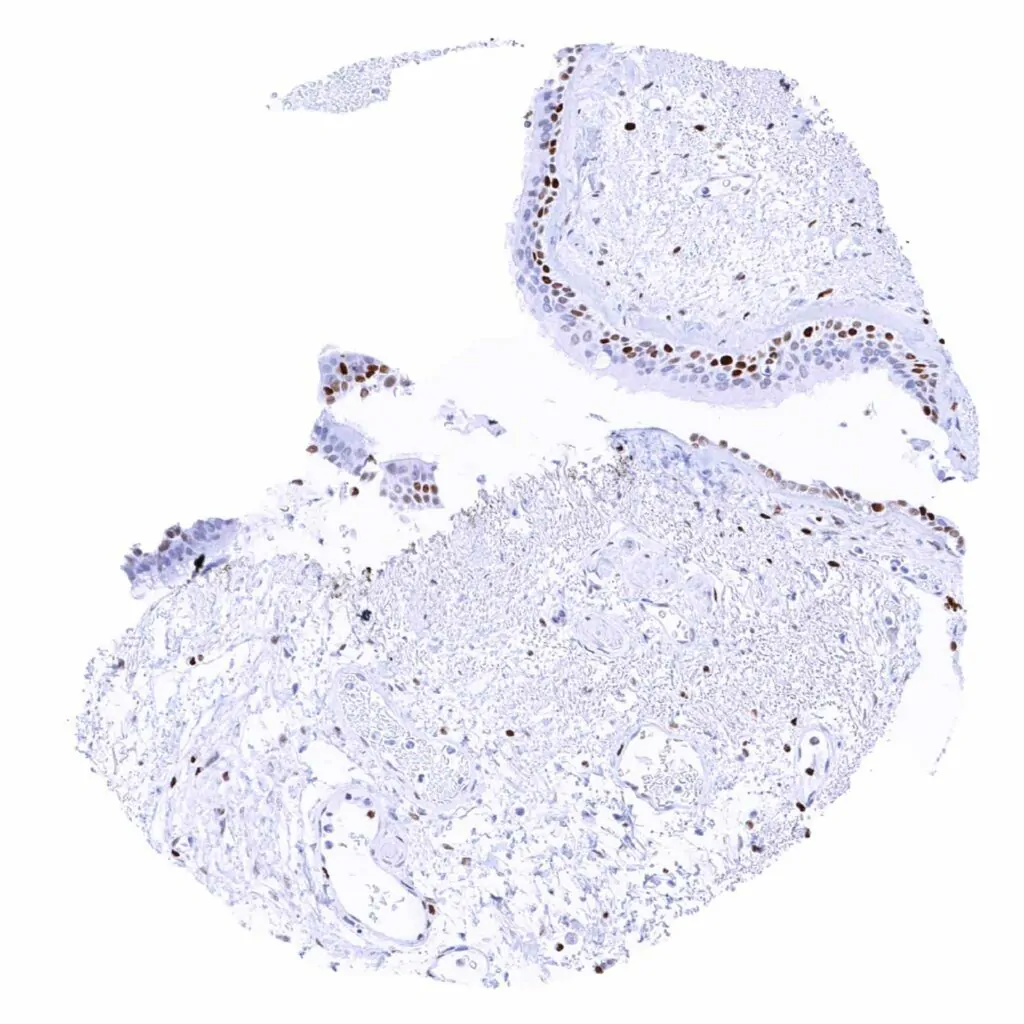

Skin – Suprabasal and basal cell layers (weaker) of the squamous epithelium show a distinct MCM2 positivity

Skin, hairfollicel and sebaceous glands – Intense MCM2 positivity of peripheral germinative cells